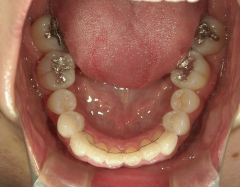

矯正歯科 治療前矯正歯科 治療前

矯正_灰色.pngno.41_8994_治療前_下.JPG矯正_灰色.png